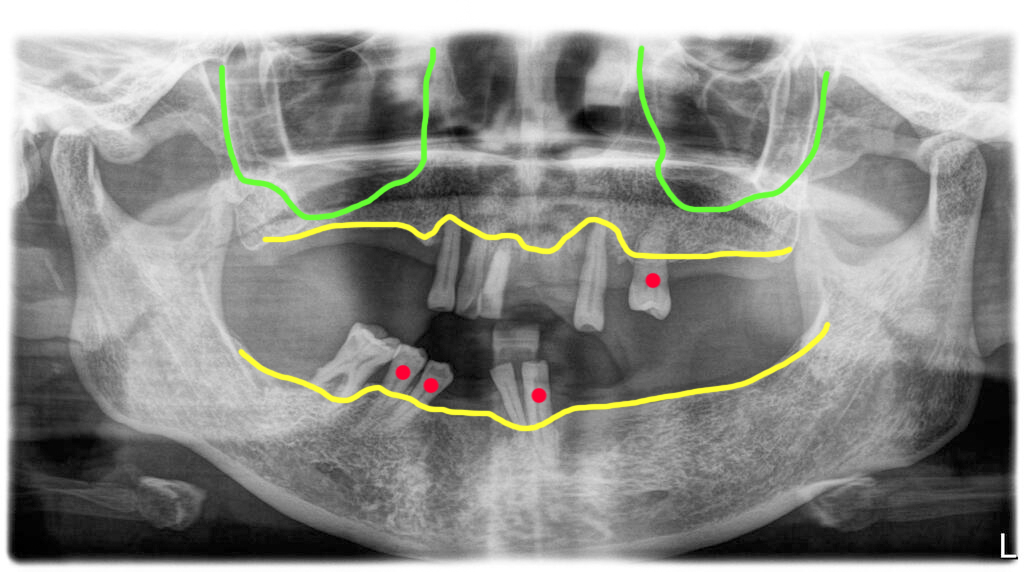

사진의 환자는 전체적으로 잇몸질환이 진행되어 이미 다수의 치아를 상실한 상태였습니다. 치아를 상실했지만 회복을 하지 않고 방치했기 때문에 남아있는 치아들이 빈 공간으로 쓰러져 있습니다.

위턱의 경우 대부분 말기 치주염으로 발치를 결정했지만 빨강색으로 표시된 치아는 중기 치주염상태로 당장 발치는 하지 않아도 되는 정도입니다.

하지만 장기적 안목으로 해당 치아를 발치하기로 했습니다. 그 이유는 해당 치아가 남아있는 상태에서 치솔질이 되지 않아서 해당 치아에 염증이 갑자기 심해지면 주변에 심어 놓은 임플란트까지 실패로 이어질 수 있기 때문입니다.

만약 한 개 남은 치아가 완전히 건강한 상태이고, 환자가 구강위생이 잘 될 수 있다고 판단이 된다면 남기는 것도 가능하지만 이 분은 뽑는 쪽이 더 좋은 경우라고 판단했습니다.

그리고 아래턱에 빨강색으로 표시된 치아들도 중기 치주염 상태이긴 하지만 위치가 너무 좋지 않고 쓰러진상태라 해당 치아를 유지하면서 전체적 치료를 했을 때 구조적이 문제가 생길 수 있어서 예지성 있게 발치를 결정했습니다.

결국 모든 치아 발거하고 전체임플란트 치료를 계획했습니다.